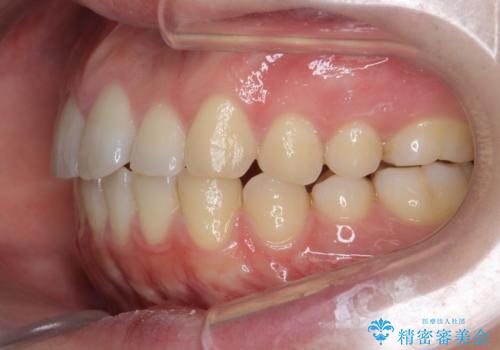

前歯が気になる。インビザラインライト

- 前歯が気になるとの事で来院。

矯正を希望されたが費用と時間を抑えたいとの事でインビザラインライトで矯正を行いました。(奥歯の位置関係はほぼ変えない)

前歯が綺麗に並び大変満足して頂けました。